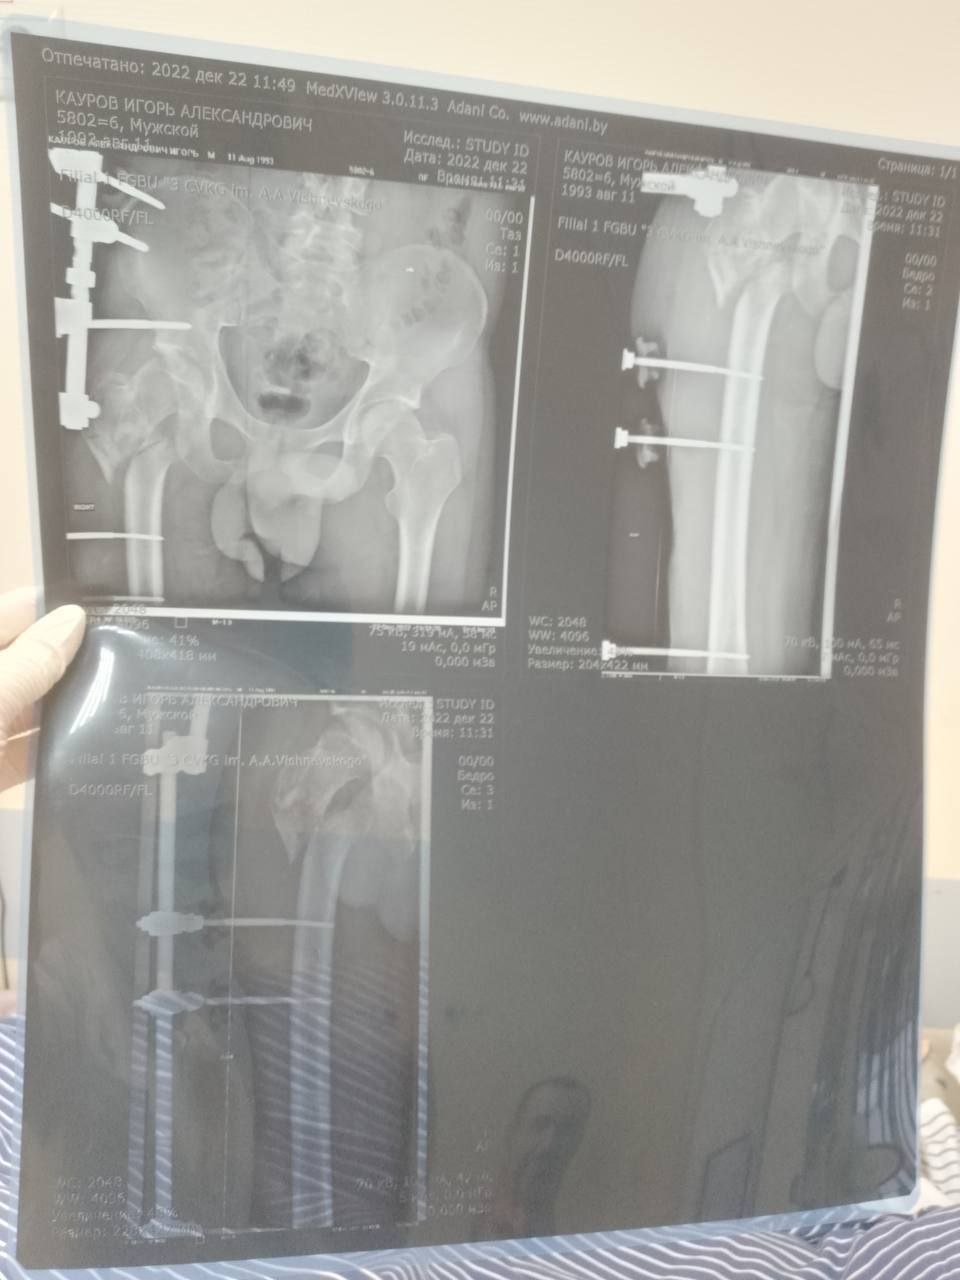

Мобилизованный 25 февраля 2022 года, он прошел через горнило Херсонщины. 28 августа 2022 года в 23:10 под ракетным обстрелом боец получил тяжелейшее ранение правого бедра. С этого момента началась эпопея спасения: Берислав, первичные обработки, эвакуация в Москву (ЦВКГ им. Вишневского), затем в Санкт-Петербург (Военно-медицинская академия им. Кирова). Множественные некрэктомии, остеосинтезы, установка штифтов, борьба с инфекцией...

Из-за обширных повреждений и многократных операций правая нога бойца стала короче левой на 8-9 сантиметров. Обычное эндопротезирование здесь было бессильно. Требовалось чудо инженерной и хирургической мысли.

Вместо стандартной замены сустава пациенту выполнили сложнейшее вмешательство с использованием ревизионных систем эндопротезирования, в ЛНР такую операцию провели впервые. Главная задача хирургов заключалась не просто в установке импланта, а в восстановлении биологической оси конечности и компенсации укорочения.